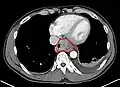

Additional testing is needed to assess how much the cancer has spread (see § Staging, below). Computed tomography (CT) of the chest, abdomen and pelvis can evaluate whether the cancer has spread to adjacent tissues or distant organs (especially liver and lymph nodes). The sensitivity of a CT scan is limited by its ability to detect masses (e.g. enlarged lymph nodes or involved organs) generally larger than 1 cm.[44][45] Positron emission tomography is also used to estimate the extent of the disease and is regarded as more precise than CT alone.[46] PET/MR as a novel modality has shown promising results in preoperative staging with fair feasibility and good correlation in comparison to PET/CT. It can enhance tissue differentiation with lowering the radiation dose to the patient.[47] Esophageal endoscopic ultrasound can provide staging information regarding the level of tumor invasion, and possible spread to regional lymph nodes.